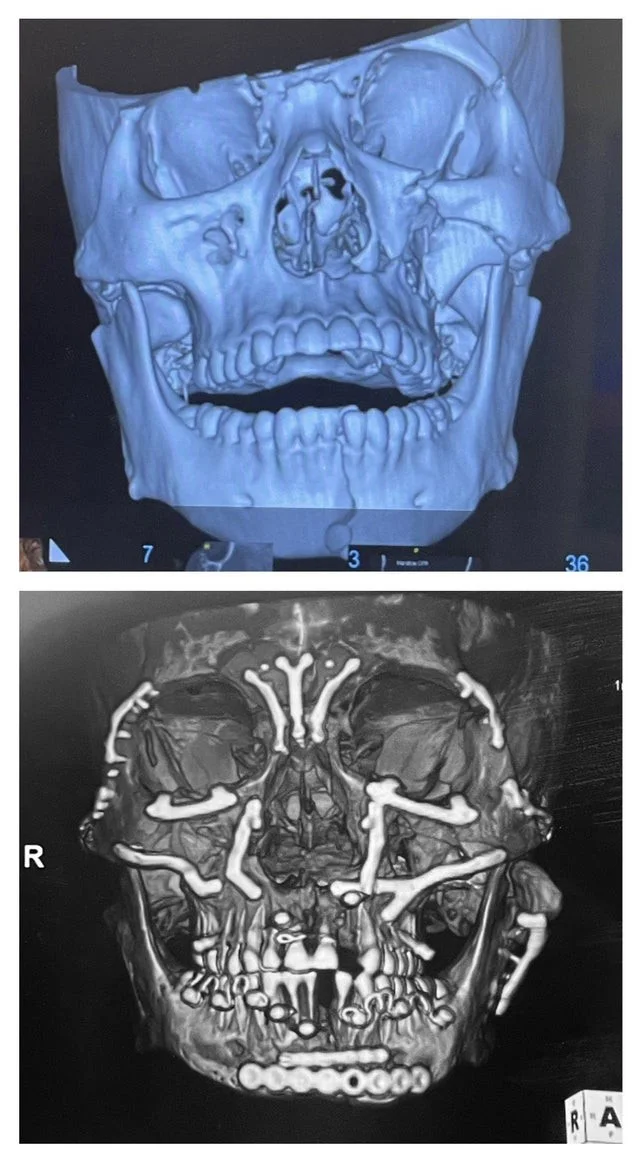

"4 месяца назад я сломал все кости на лице: 90 винтов и 30 пластин спустя я на пути к выздоровлению"